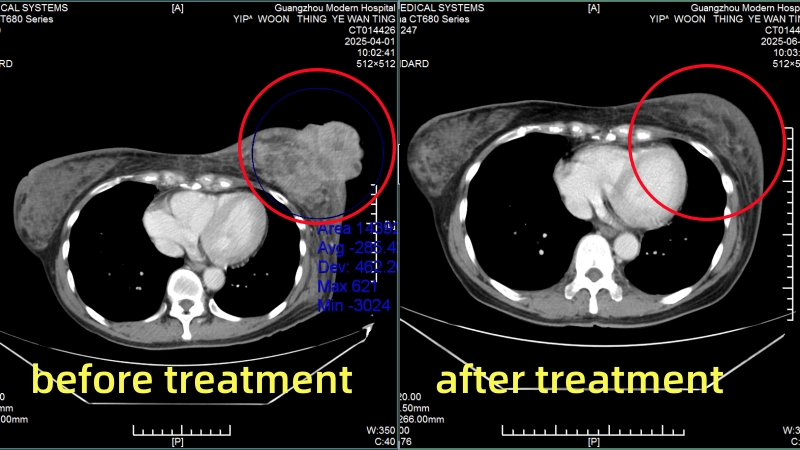

Yip Woon Thing

(Yip Woon Thing)

(Before treatment VS After first treatment)